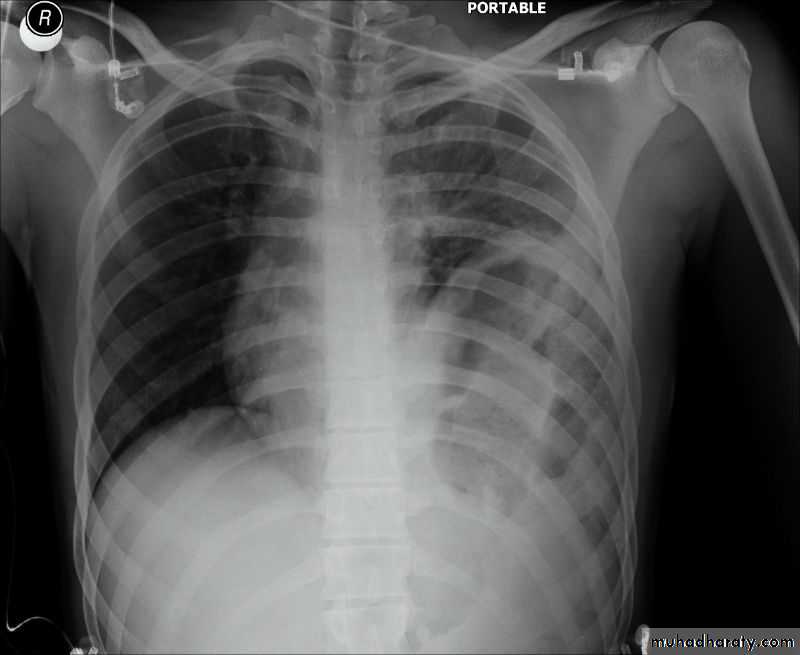

Pneumothorax

!! pneumothorax

Area of hypertranslucensy (pneumothorax)